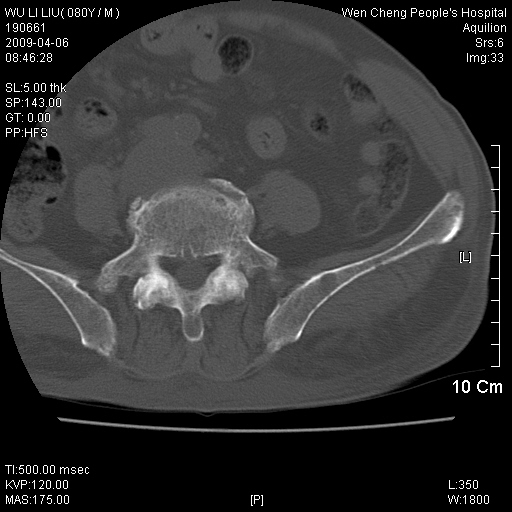

以下是引用zjzjr在2009-4-7 12:13:00的发言:[br]支持多发性转移瘤,右股骨颈骨折,腰椎亦有压缩性骨折.肝内胆管结石伴胆内外胆管扩张,左肾结石.

以下是引用liaoqiang在2009-4-7 8:44:00的发言:[br]考虑多发性骨髓瘤伴肝肺转移、肝内胆管结石、左肾结石、右股骨颈骨折。

以下是引用余辉在2009-4-7 8:52:00的发言:[br]椎骨及骨盆骨质疏松,骨破坏主要累及椎体,各骨破坏较广泛,各病灶边缘均较清晰锐利,血沉增快,白细胞增高.支持考虑多发骨髓瘤,建议查本尿周氏蛋白.[br]胆内胆管及左肾结石[br]右股骨颈骨折,考虑病理性